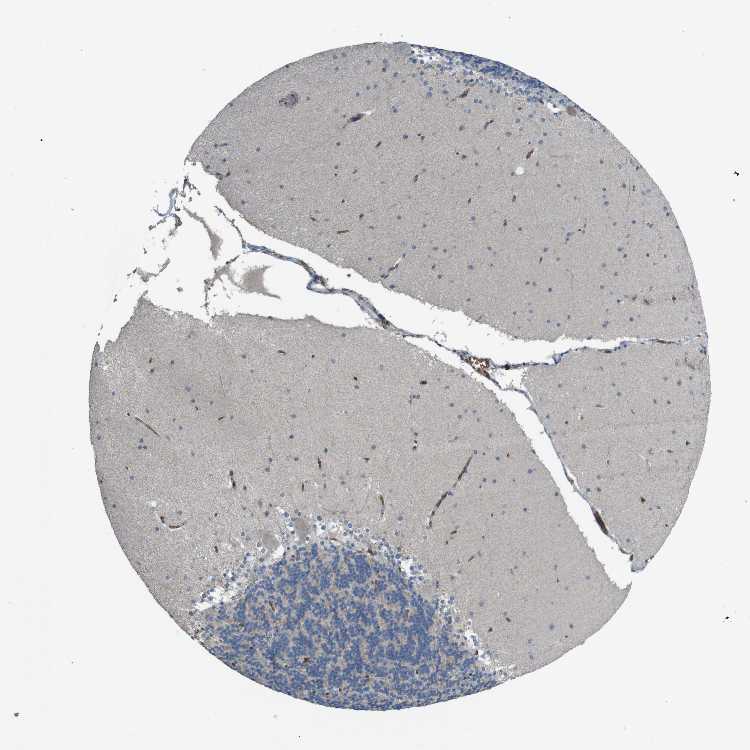

BRAIN CEREBELLUM Show tissue menu

CEREBELLUM - Expression summary

CEREBELLUM - Antibody stainingi

Antibody staining in the annotated cell types in the current human tissue is reported as not detected, low, medium, or high, based on conventional immunohistochemistry profiling in selected tissues. This score is based on the combination of the staining intensity and fraction of stained cells.

Each image is clickable and will lead to virtual microscopy that enables deeper exploration of all samples and also displays staining intensity scores, fraction scores and subcellular localization as well as patient and tissue information for each sample.

Antibody HPA014811Antibody CAB002658

Purkinje cells Not detectedNot detected

Cells in granular layer Not detectedNot detected

Cells in molecular layer Not detectedNot detected